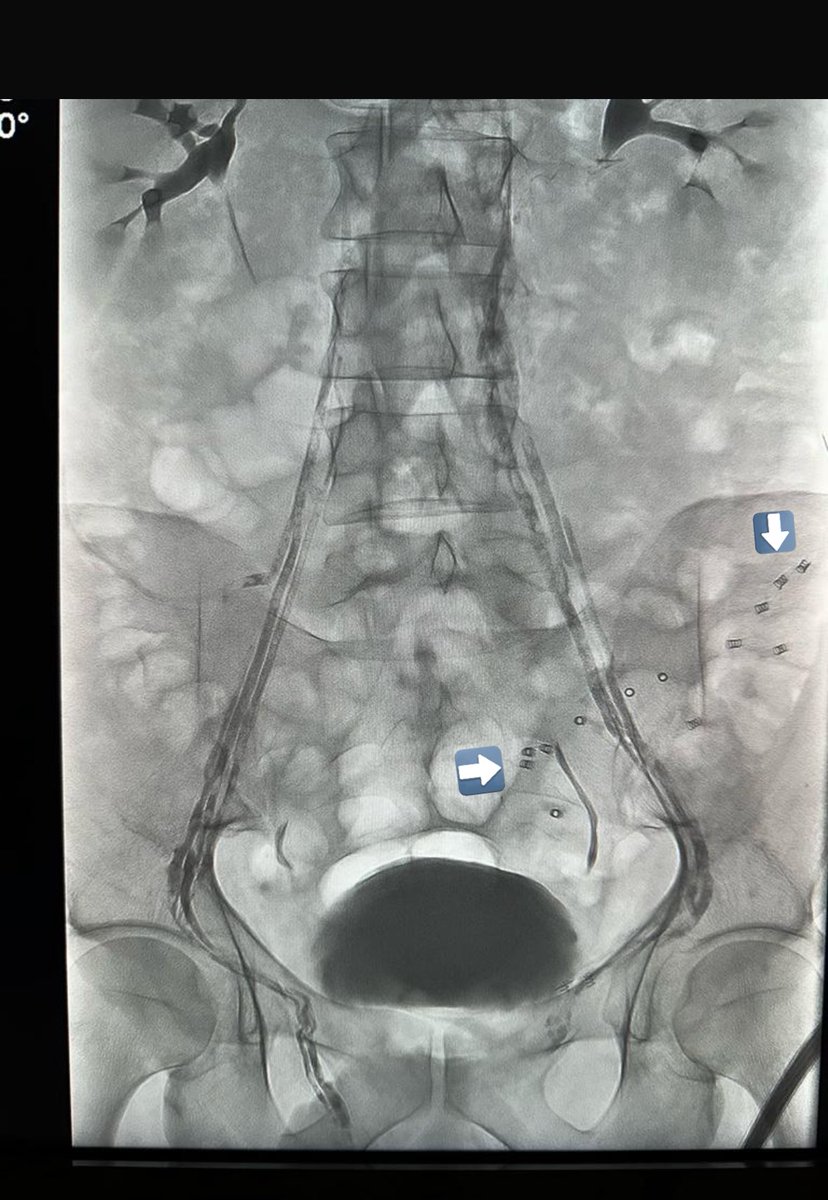

٢٣- هل القسطرة تعمل بطريقة واحدة؟ كما قلنا مسبقاً يتم اغلاق الوريد الخصوي باللفائف المعدنية او الصمغ الطبي. الاختيار يكون غالباً بناءً على خبرة الطبيب ، توفر الادوات ، التكلفة ، و كذلك حجم ومواقع الأوردة الخصوية. هذه الدراسة وضحت أن الصمغ الطبي هو أفضل خيار بأقل نسبة عودة للدوالي (بسبب تغلغله بالأوردة). كذلك الصمغ الطبي يختفي مع الوقت ولا يبقى له أثر بالأشعة (بخلاف الخيوط الجراحية واللفائف). ماهي عيوبه؟ تكلفته أعلى في بعض المراكز الطبية ويحتاج الى خبرة. بالأسفل صورة لمريض قد سبق وعملت له جراحة فتق إربي(موضح كلبسات تثبيت الشبكة) ، تم تحويله للقسطرة (لاحظ كيف يتغلغل الصمغ الطبي بالأوردة) بحكم أن الجراحة السابقة تزيد من نسبة حصول المضاعفات خاصة موت الخصية.